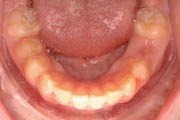

Crowding

Before